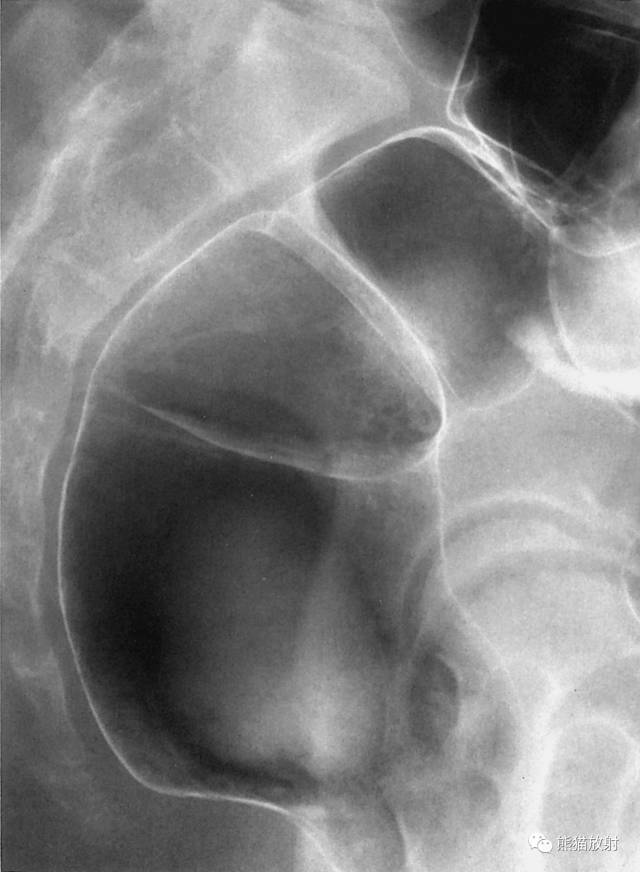

9 Spot Film of the Ileocecal Region 回盲部( 点片 )

1 Haustra of the colon 结肠袋,2 Ascending colon 升结肠,3 Ileum 回肠,4 Ileocecal valve 回盲瓣,5 Terminal ileum 末端回肠,6 Cecum 盲肠